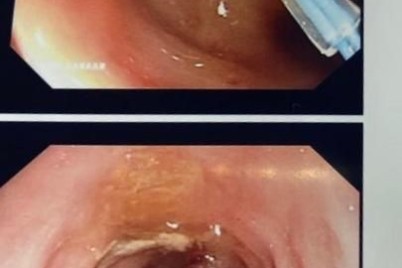

الطائف - هلال اليزيدي نجح مجمع الملك فيصل بالطائف في اكتشاف "ورم" نادر وعالي الخطورة لدى شاب يبلغ من...